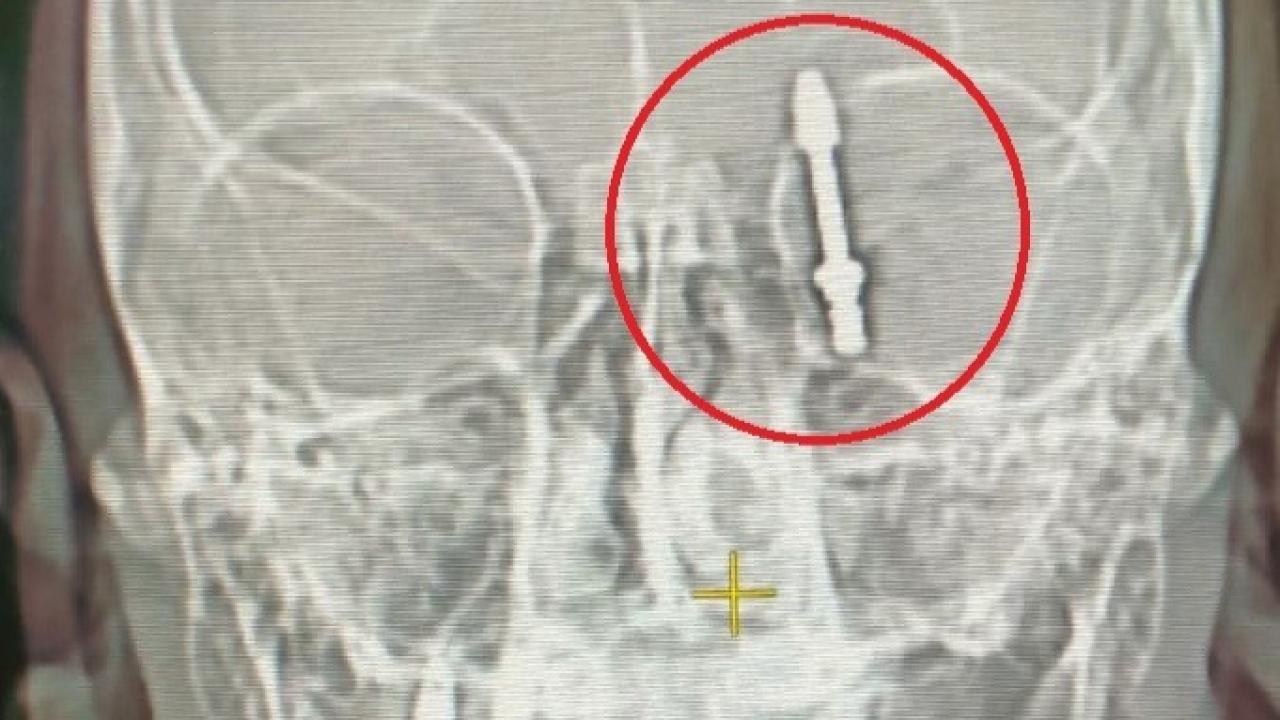

Bursa’nın Nilüfer ilçesinde yaşanan olay, bir diş tedavisinin nasıl hayatı kabusa çevirebileceğini gözler önüne serdi. Fabrika işçisi Ramazan Yılmaz (40), dişlerinin sallandığı gerekçesiyle özel bir klinikte muayene oldu. Doktor A.D. tarafından önerilen implant tedavisi, Yılmaz’ın hayatını tehlikeye attı. İddiaya göre, doktorun hatalı müdahalesi sonucu implant vidası çene kemiğini delip kafatasına saplandı.

Baygınlık geçiren Yılmaz, kliniğin kendi aracıyla hastaneye kaldırıldı. Tomografi sonuçları, vidanın beynine kadar ilerlediğini ortaya koydu. Acil olarak ameliyata alınan talihsiz adam, saatler süren operasyonla ölümden döndü. Operasyonu gerçekleştiren sağlık ekibi, hayatını kurtardı ancak yaşananlar Yılmaz’ı hem fiziksel hem de psikolojik olarak derinden etkiledi.